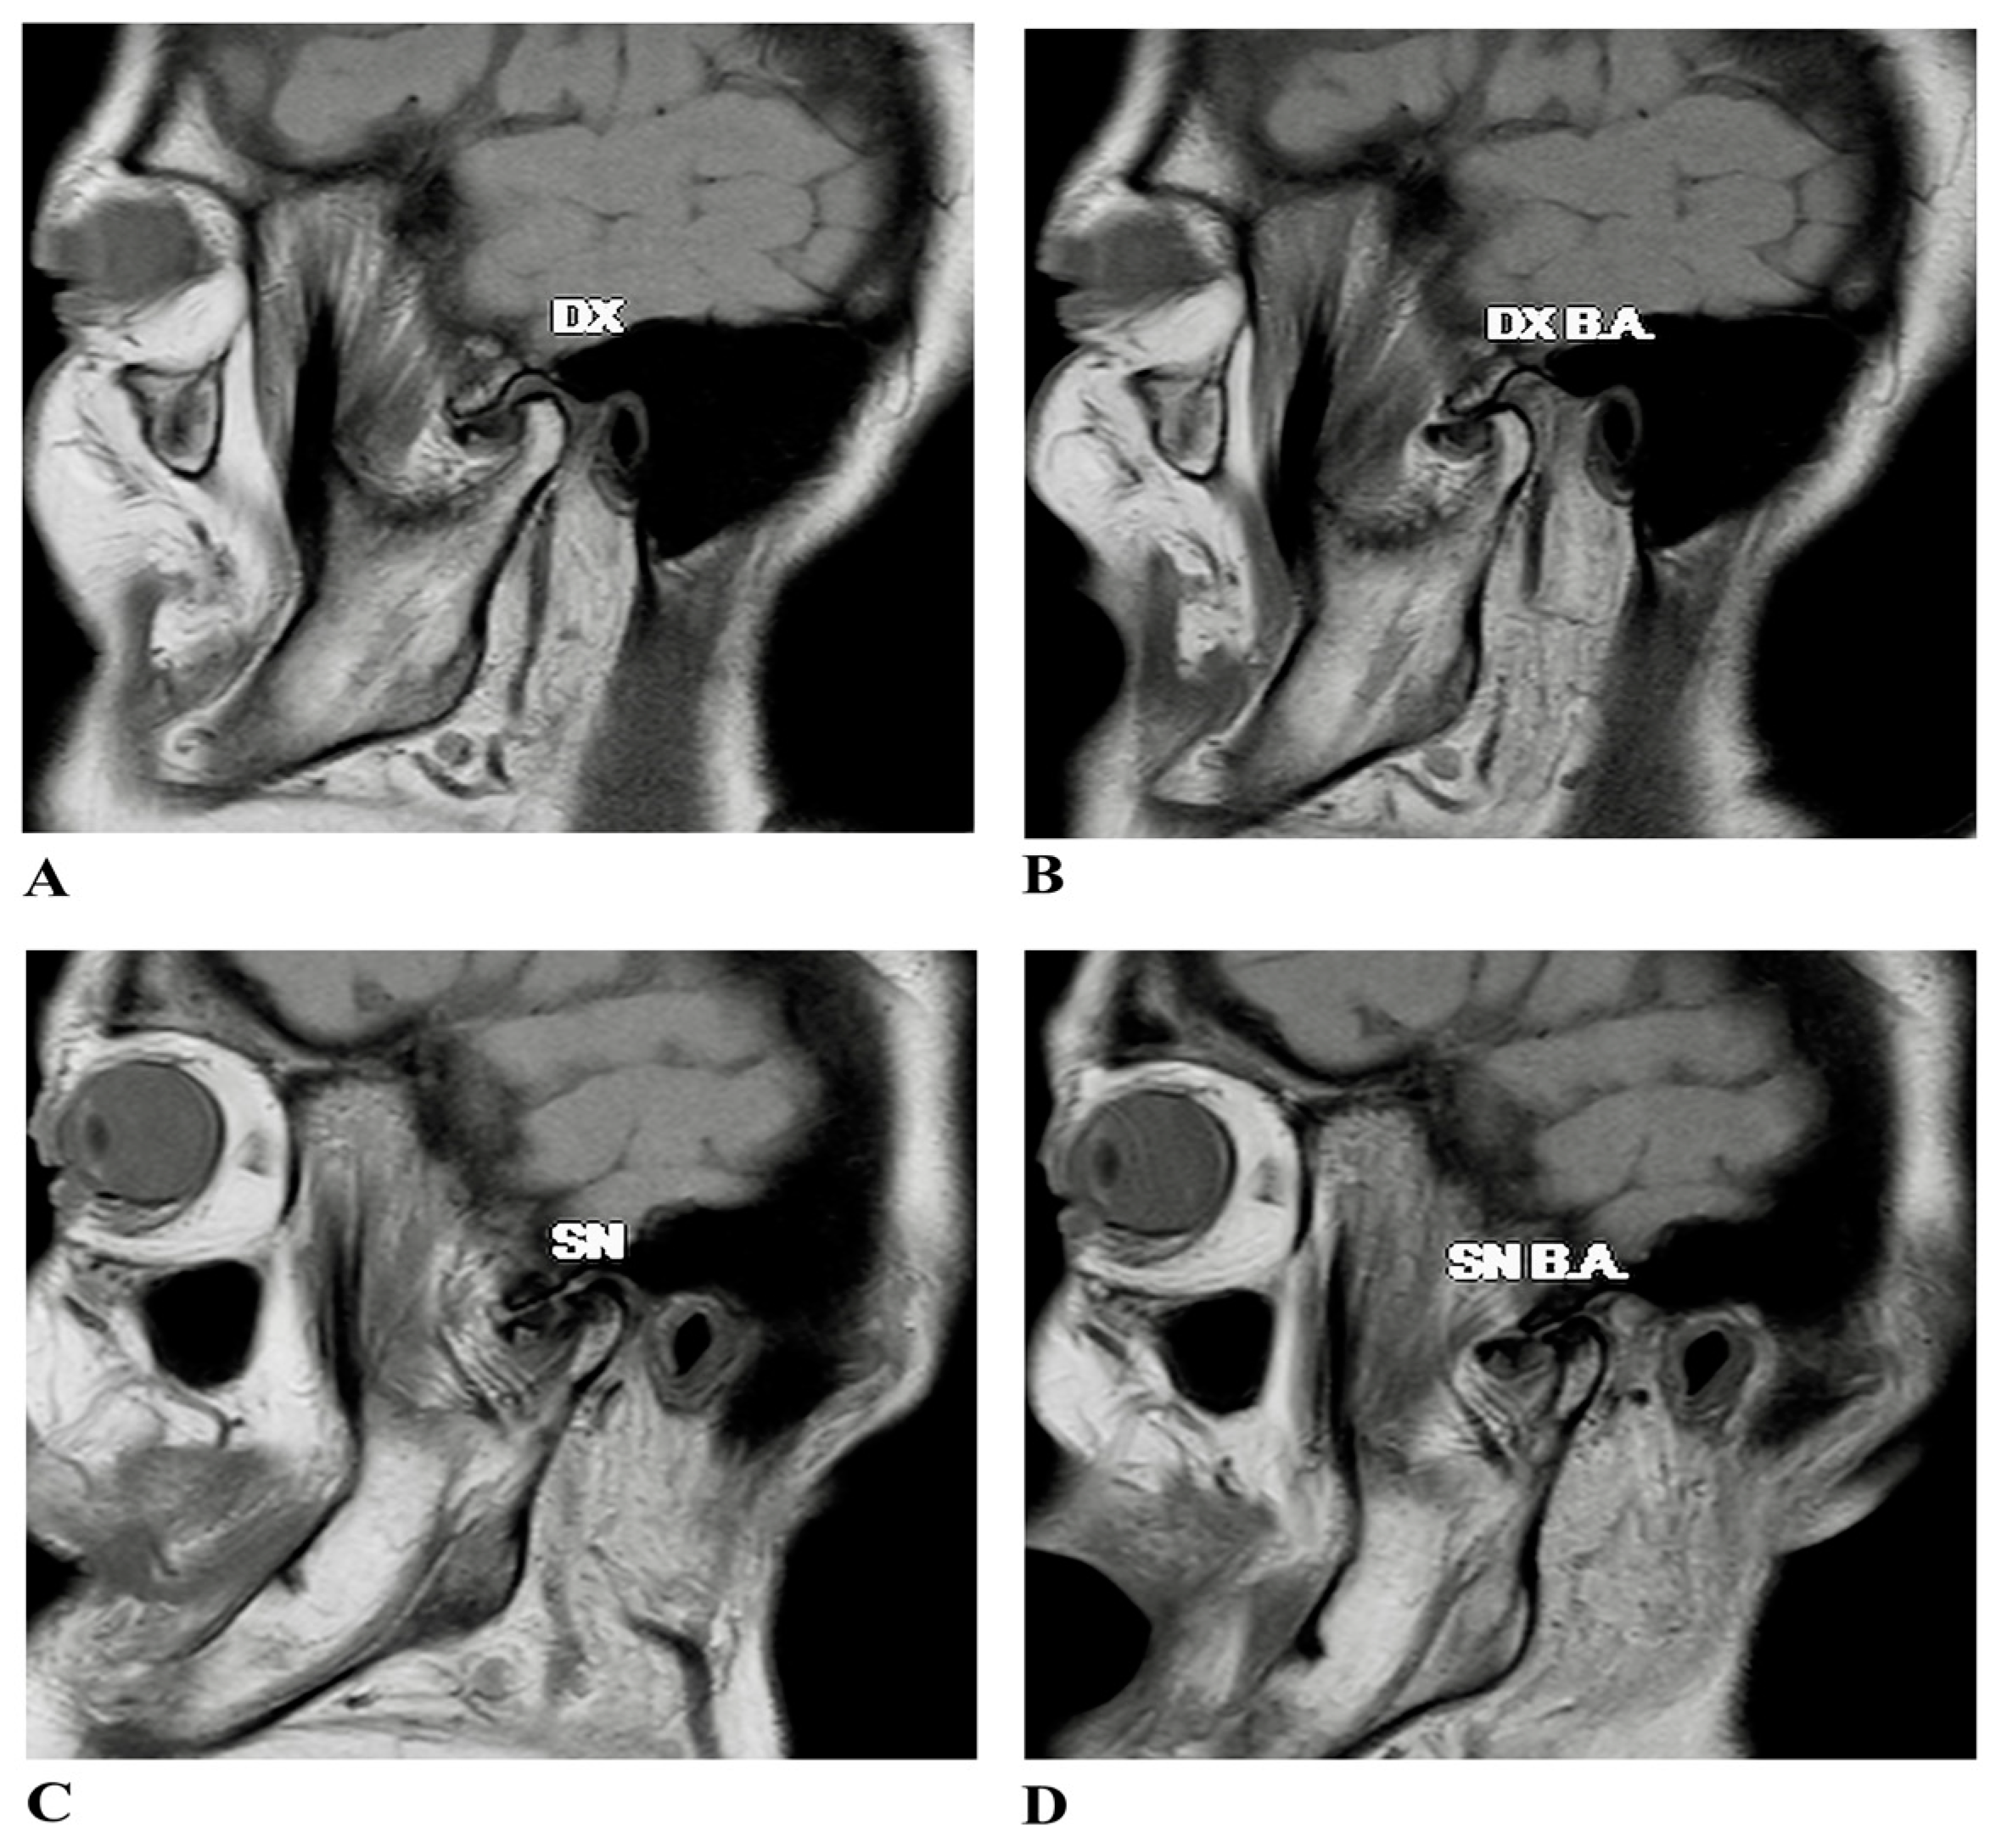

2.1. Case Presentation

- Shen, P.; Huo, L.; Zhang, S.Y.; Yang, C.; Cai, X.Y.; Liu, X.M. Magnetic Resonance Imaging Applied to the Diagnosis of Perforation of the Temporomandibular Joint. J. Cranio-Maxillo-Facial Surg. 2014, 42, 874–878. [Google Scholar] [CrossRef]

- Kim, J.-Y.; Jeon, K.-J.; Kim, M.-G.; Park, K.-H.; Huh, J.-K. A Nomogram for Classification of Temporomandibular Joint Disk Perforation Based on Magnetic Resonance Imaging. Oral Surg. Oral Med. Oral Pathol. Oral Radiol. 2018, 125, 682–692. [Google Scholar] [CrossRef]

- Kuribayashi, A.; Okochi, K.; Kobayashi, K.; Kurabayashi, T. MRI Findings of Temporomandibular Joints with Disk Perforation. Oral Surg. Oral Med. Oral Pathol. Oral Radiol. Endod. 2008, 106, 419–425. [Google Scholar] [CrossRef]

- Yura, S.; Nobata, K.; Shima, T. Diagnostic Accuracy of Fat-Saturated T2-Weighted Magnetic Resonance Imaging in the Diagnosis of Perforation of the Articular Disc of the Temporomandibular Joint. Br. J. Oral Maxillofac. Surg. 2012, 50, 365–368. [Google Scholar] [CrossRef] [PubMed]